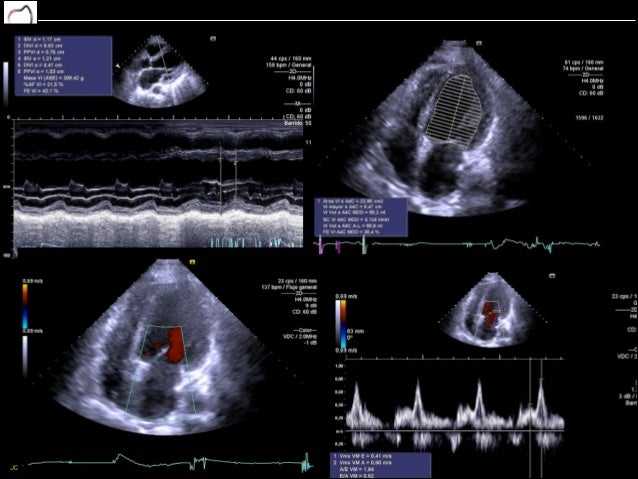

Cardiotoxicidad inducida por quimioterapia.

Cardiotoxicidad por quimioterapia en el Instituto Nacional de Enfermedades Neoplásicas

Cardiotoxicidad inducida por quimioterapia

Periprocedural anticoagulation management of patients with venous thromboembolism. Apresentam atividade antitumoral significativa contra o carcinoma do colo uterino, linfomas e quimioterapis testiculares 4. Arterial pulse pressure variation predicting fluid responsiveness in critically ill patients. Cardiotoxicity is a known adverse event of oncologic therapy that many times limits a correct regimen of administration thus lowering efficacy; therefore, understanding pathophysiological and molecular bases is essential in order to determine preventive and therapeutical measures quimioterspia can allow a reduction in the incidence of toxicity, without interfering in the efficacy of the cancer therapy.